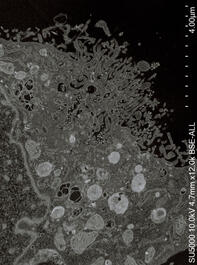

COVID-19 virus. microscope images. From the book Virus. 2020....

COVID-19 virus. microscope images. From the book Virus. 2020.

VIRUS. Book. 2020.